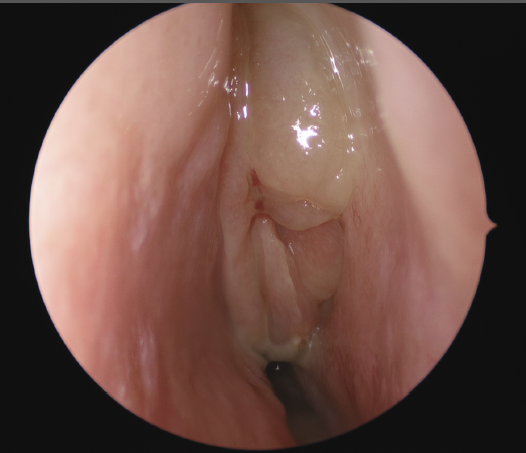

Image of inside the nose viewed with help of a inserted camera

Chronic rhinosinusitis afflicts over 30 million patients in the USA annually, or roughly 12.5% of the population. It has tremendous impacts on the economy and on a patient’s quality of life.  It is defined as symptoms of sinonasal inflammation lasting at least twelve consecutive weeks with corresponding objective physical findings. Symptoms may include nasal obstruction, congestion, nasal drainage, post-nasal drip, facial pressure, loss of smell and/or taste, fever, fatigue, and dental pain. To examine for sinonasal inflammation your physician will use a nasal endoscope to evaluate your nasal cavities and paranasal sinuses. You may also undergo computed tomography (CT) or another form of imaging.

Image of nasal endocopesThere are many causes of chronic rhinosinusitis and the specific cause in any one patient is likely multifactorial. Contributors to the disease process may be environmental, anatomic, congenital, immune, or infectious in nature.